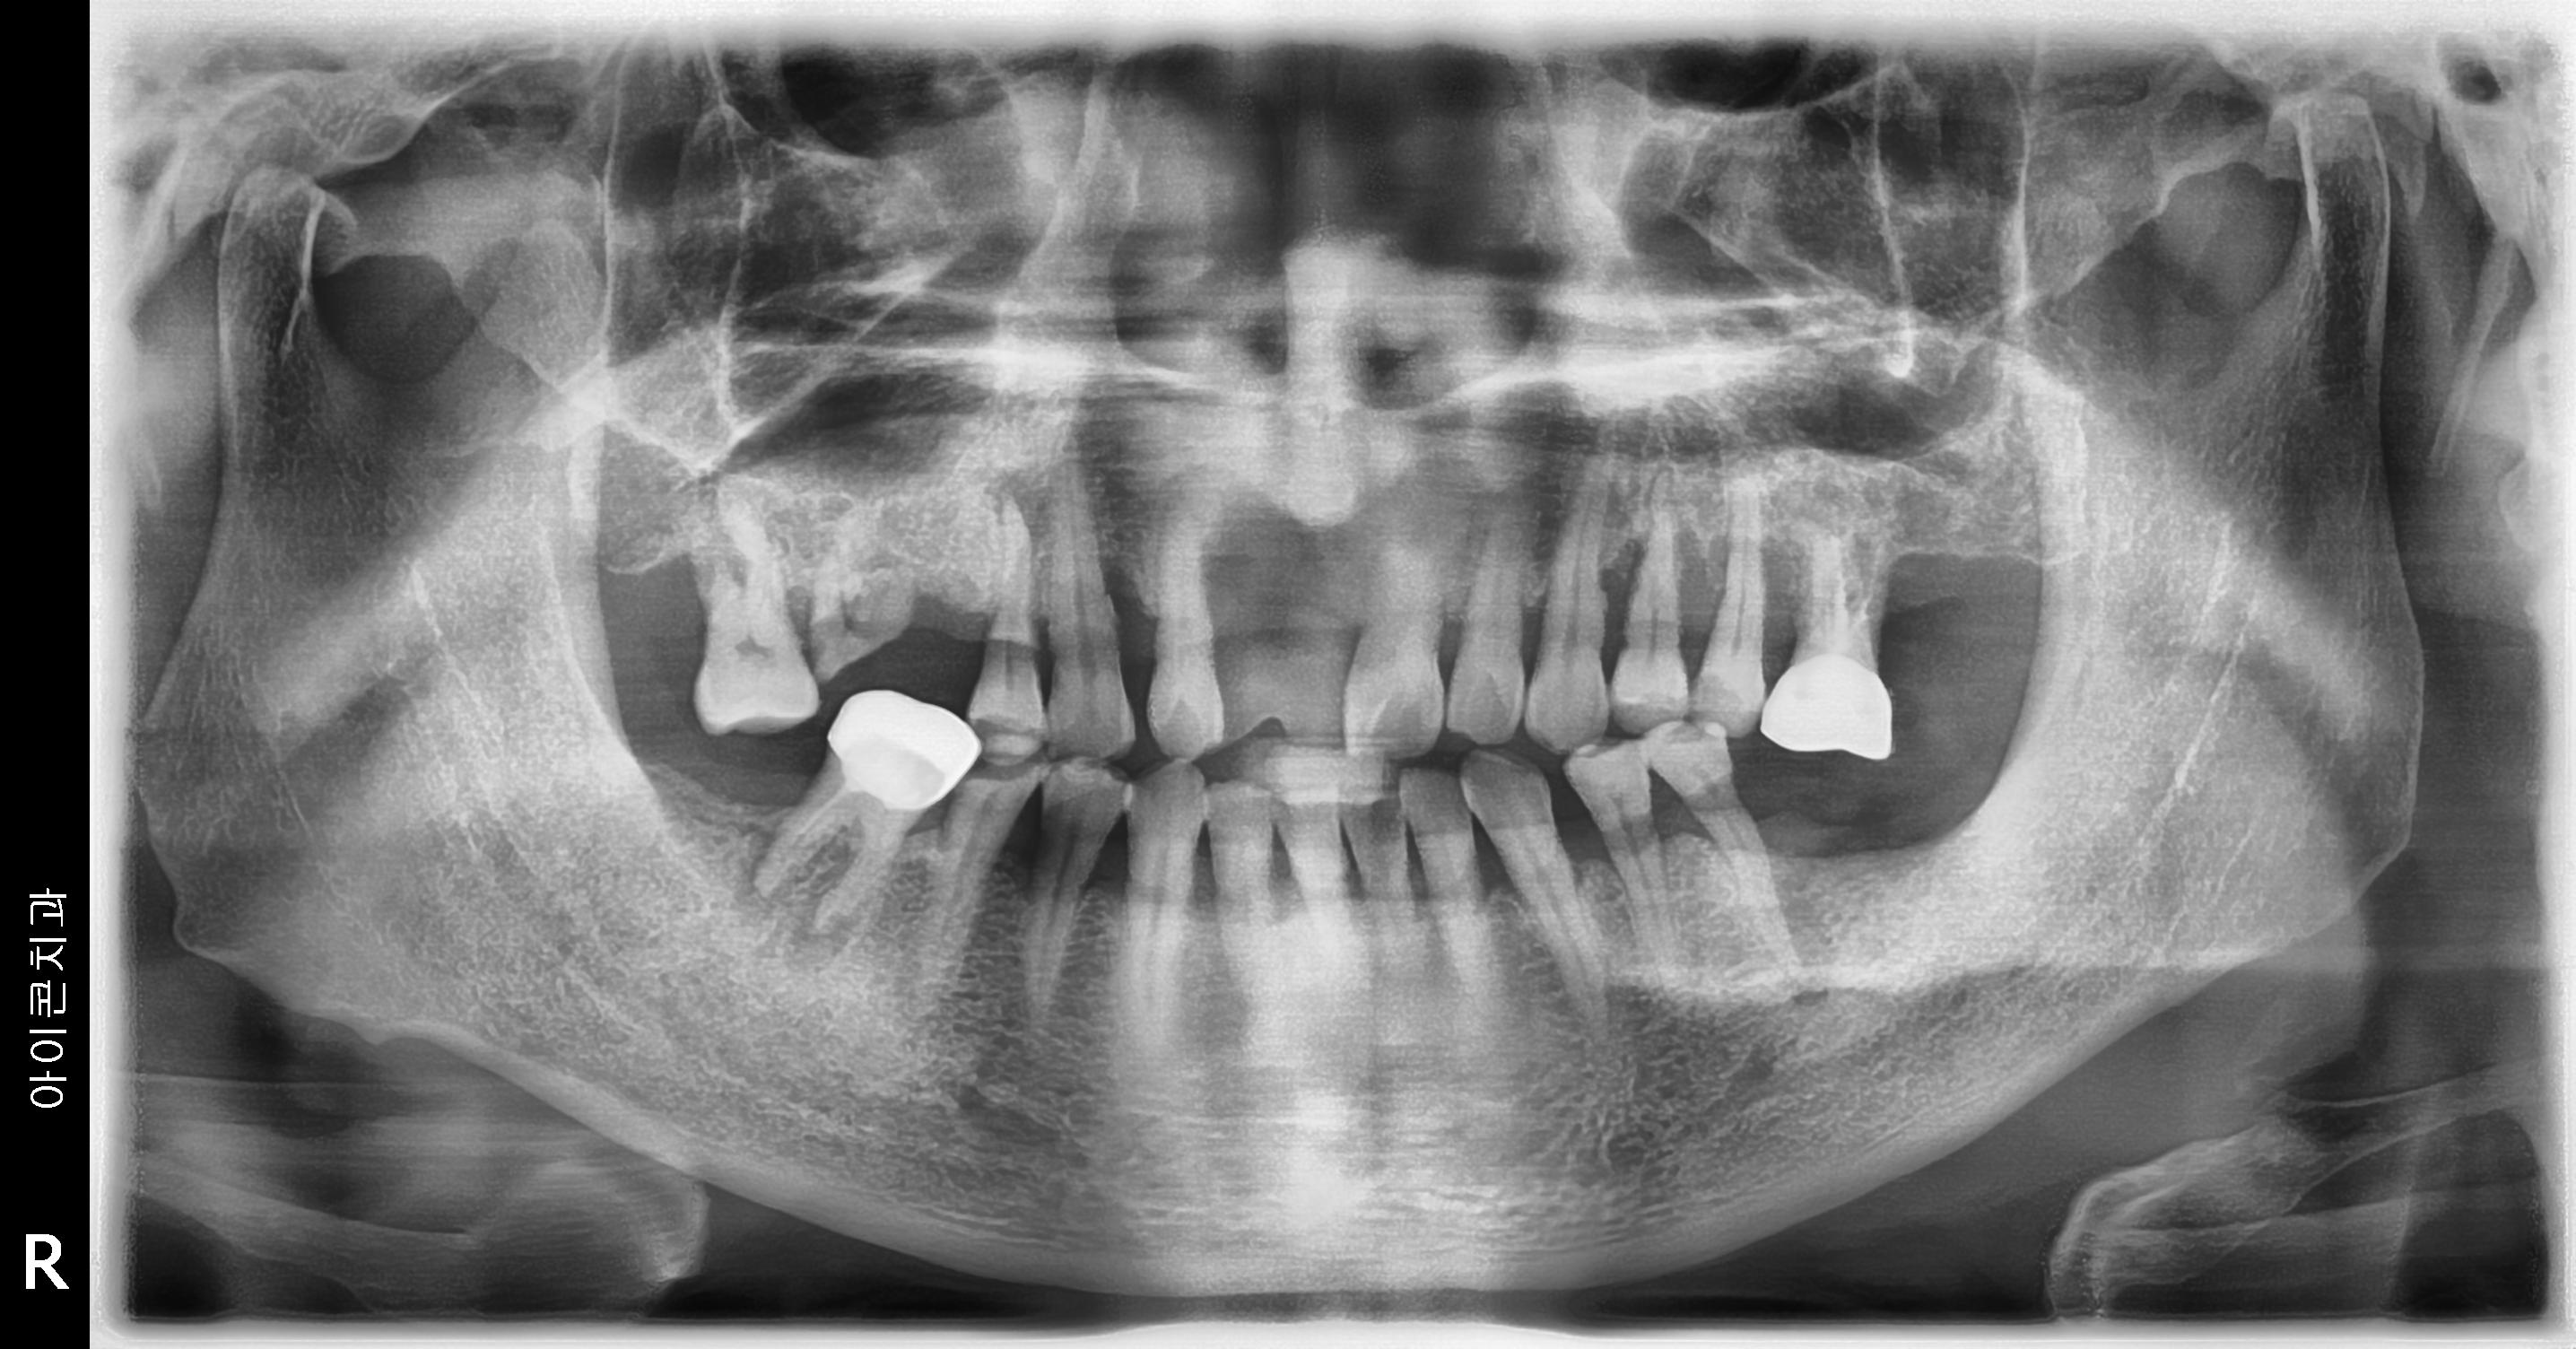

수술 전

수술 후

우측 임플란트 식립 사례

전후사진